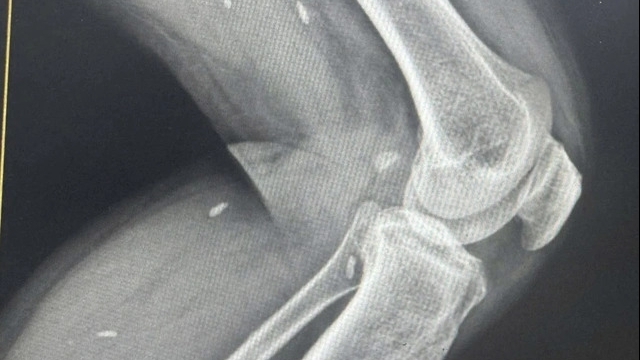

| Tổn thương phổi của bệnh nhân Covid-19 đã qua đời có nhiều tương đồng với nạn nhân của SARS năm 2003. Ảnh: Bloomberg. |

Theo nghiên cứu của The Lancet, các triệu chứng bệnh lý của Covid-19 rất nhiều điểm tương đồng với SARS và MERS. Ngoài ra, mẫu sinh thiết gan của bệnh nhân cho thấy ông bị gan nhiễm mỡ độ trung bình.

Hình ảnh X-quang của bệnh nhân cho thấy phổi bị tổn thương nhanh và có một số điểm khác biệt giữa hai bên phổi. Ngoài ra, các thay đổi mô học trong tim khiến các nhà nghiên cứu đặt giả thuyết bộ phận này bị virus corona tàn phá.